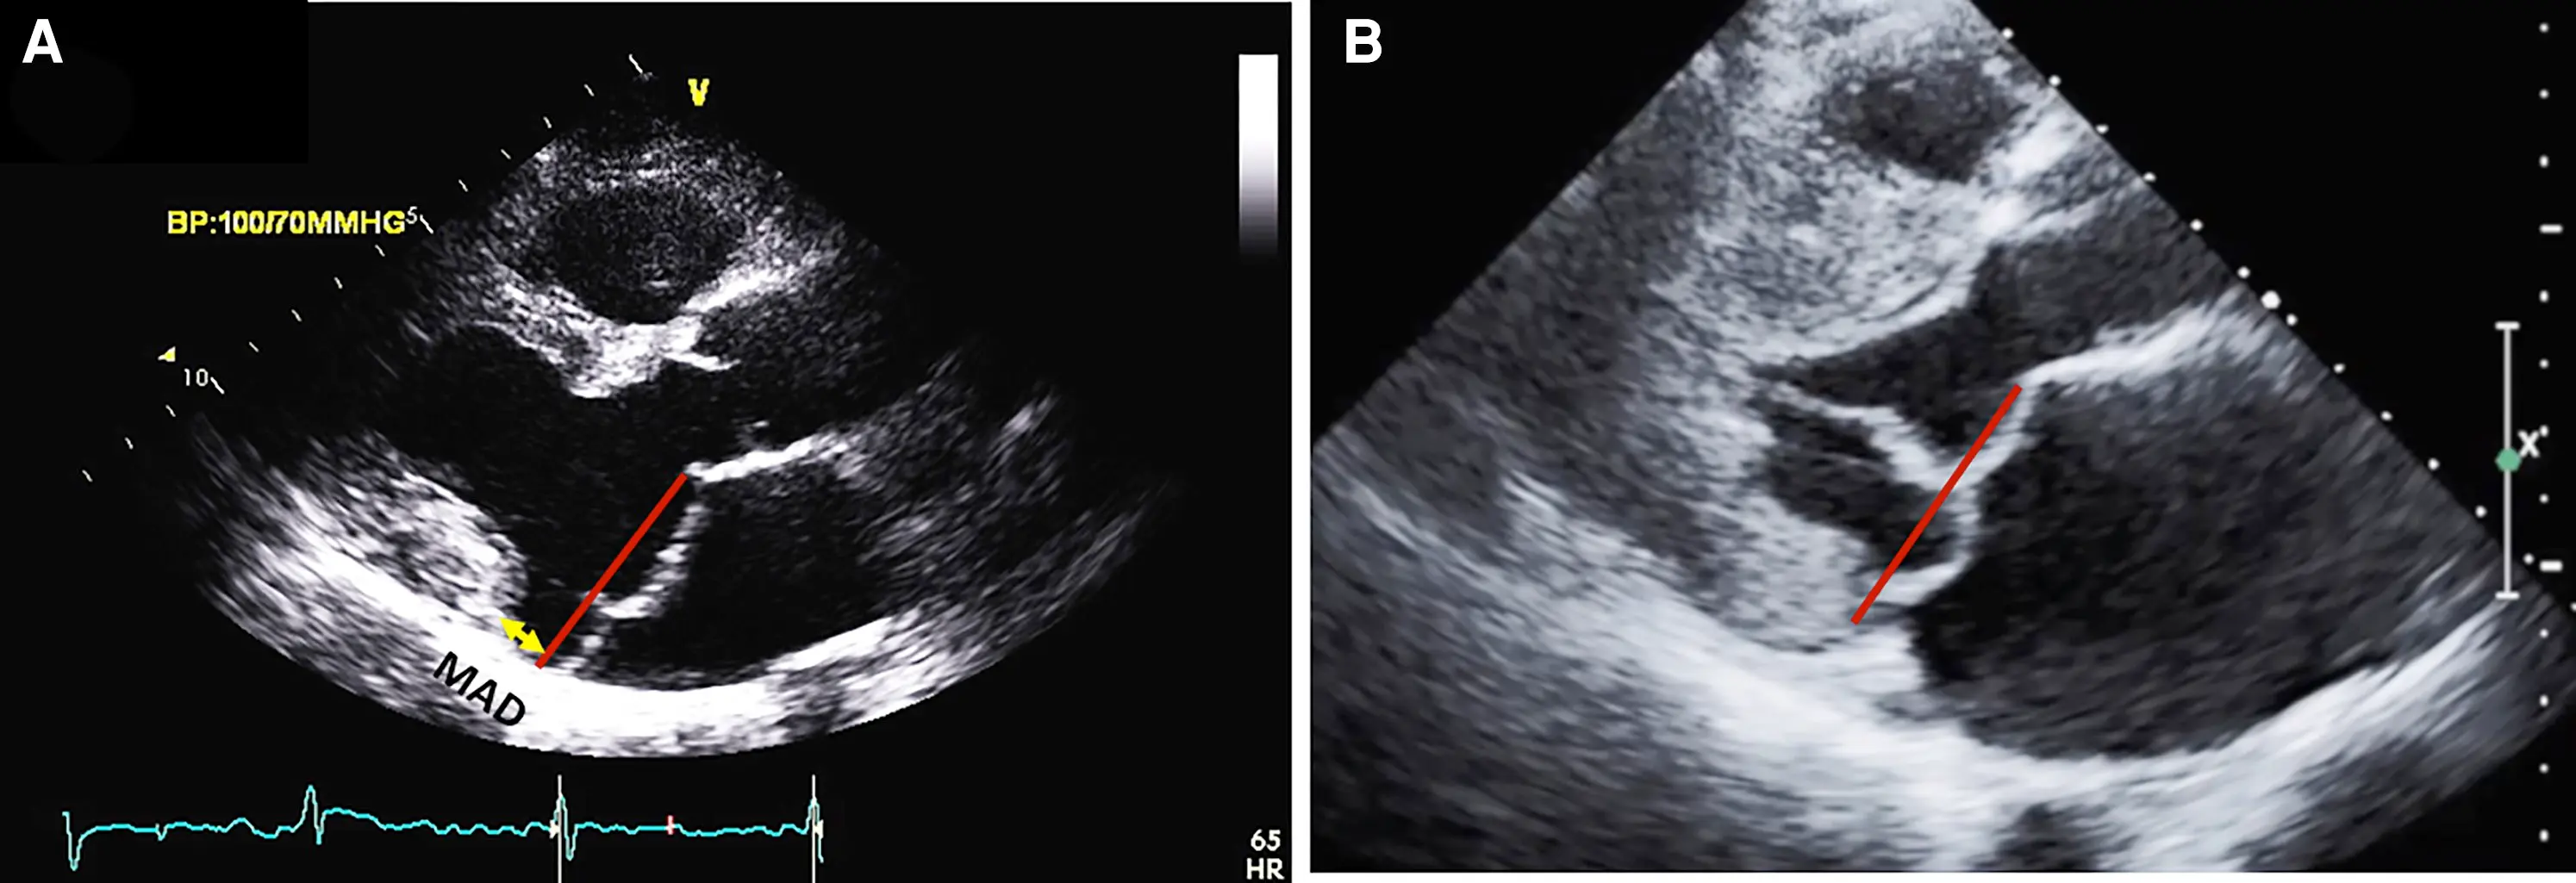

• MAD length is measured in the parasternal long axis view (or equivalent sagittal views on CMR), from the insertion of the posterior leaflet on the detached mitral annulus to the border of the bulging LV myocardium.

Figure source: 1. TTE long-axis view in end-systole displaying bileaflet mitral valve prolapse with (A) MAD (yellow line) of 11 mm length vs. (B) without MAD. The red line indicates the plane of the mitral annulus.